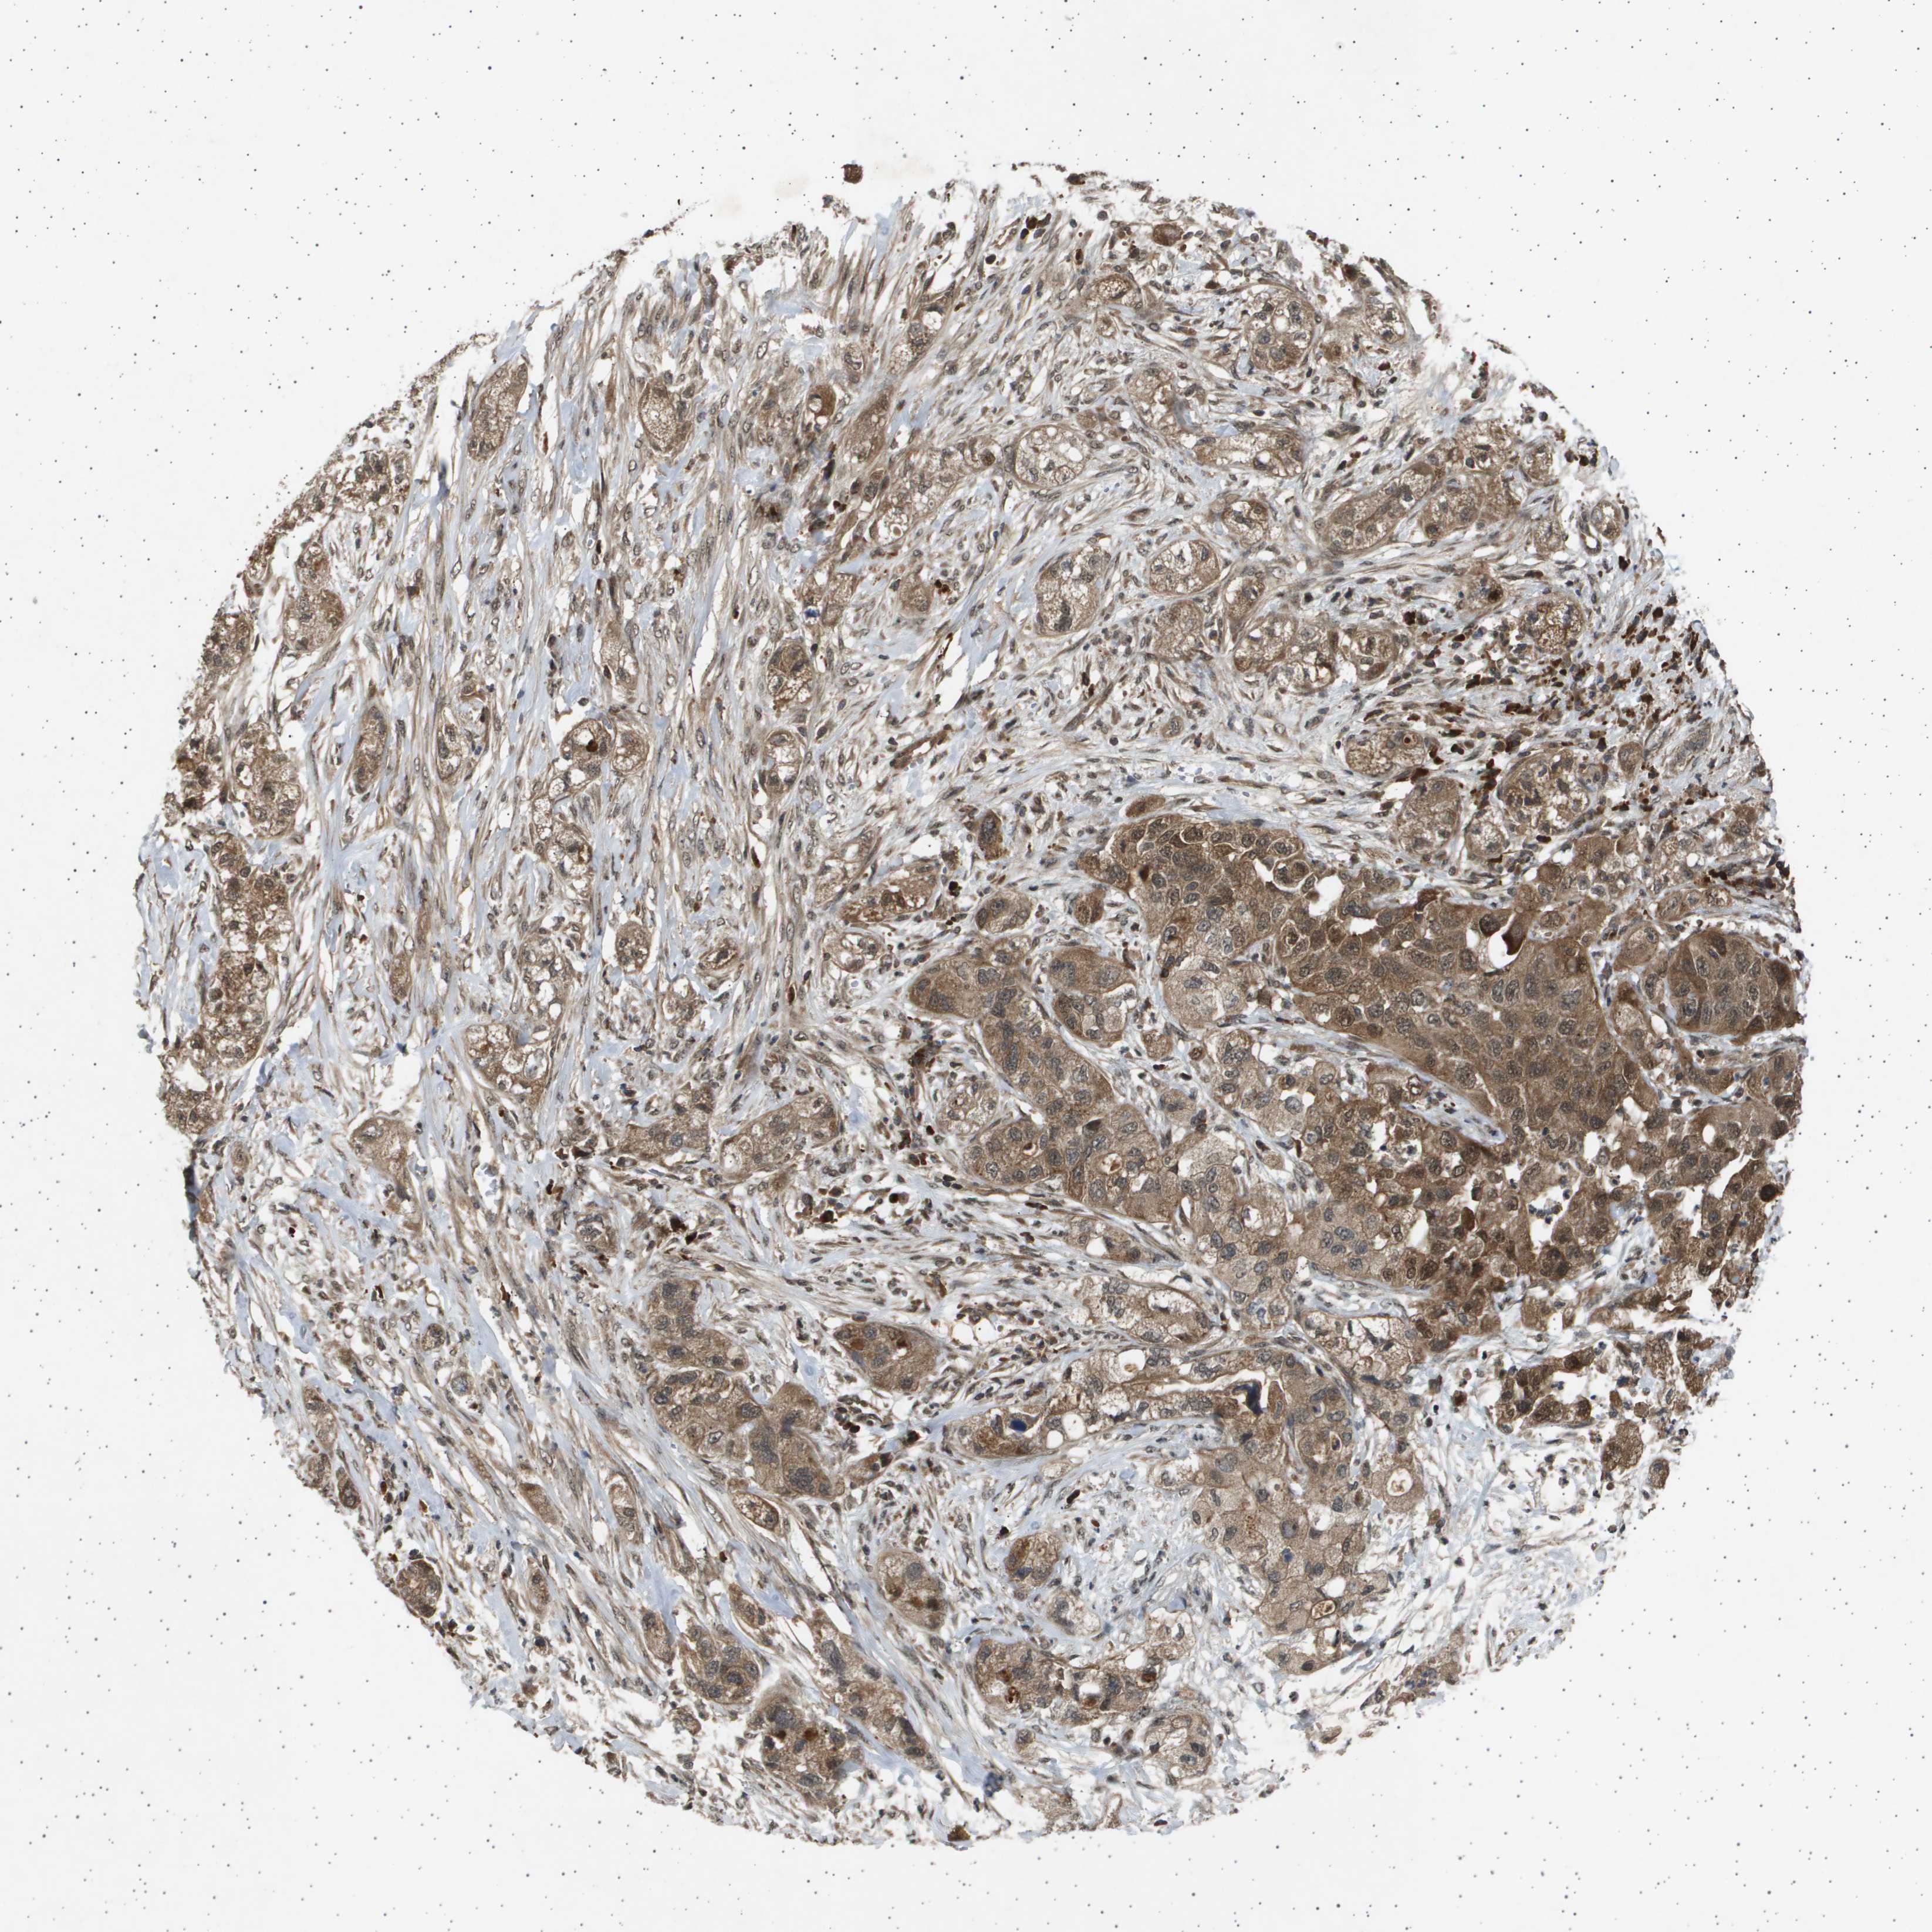

PANCREATIC CANCER - Protein expressioni

A mouse-over function shows sample information and annotation data. Click on an image to view it in a full screen mode. Samples can be filtered based on level of antibody staining by selecting one or several of the following categories: high, medium, low and not detected. The assay and annotation is described here.

Note that samples used for immunohistochemistry by the Human Protein Atlas do not correspond to samples in the TCGA dataset.

Antibody stainingi

Antibody staining in the annotated cell types in the current human tissue is reported as not detected, low, medium, or high, based on conventional immunohistochemistry profiling in selected tissues. This score is based on the combination of the staining intensity and fraction of stained cells.

Each image is clickable and will lead to virtual microscopy that enables deeper exploration of all samples and also displays staining intensity scores, fraction scores and subcellular localization as well as patient and tissue information for each sample.

Antibody HPA017869

Staining

High

Medium

Low

Not detected

Intensity

Strong

Moderate

Weak

Negative

Quantity

>75%

75%-25%

<25%

None

Location

Nuclear

Cytoplasmic/membranous

Cytoplasmic/membranous,nuclear

Adenocarcinoma, NOS